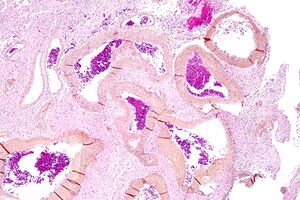

| صورة مجهرية لتشوه شرياني وريدي في المخ. HPS stain. | |